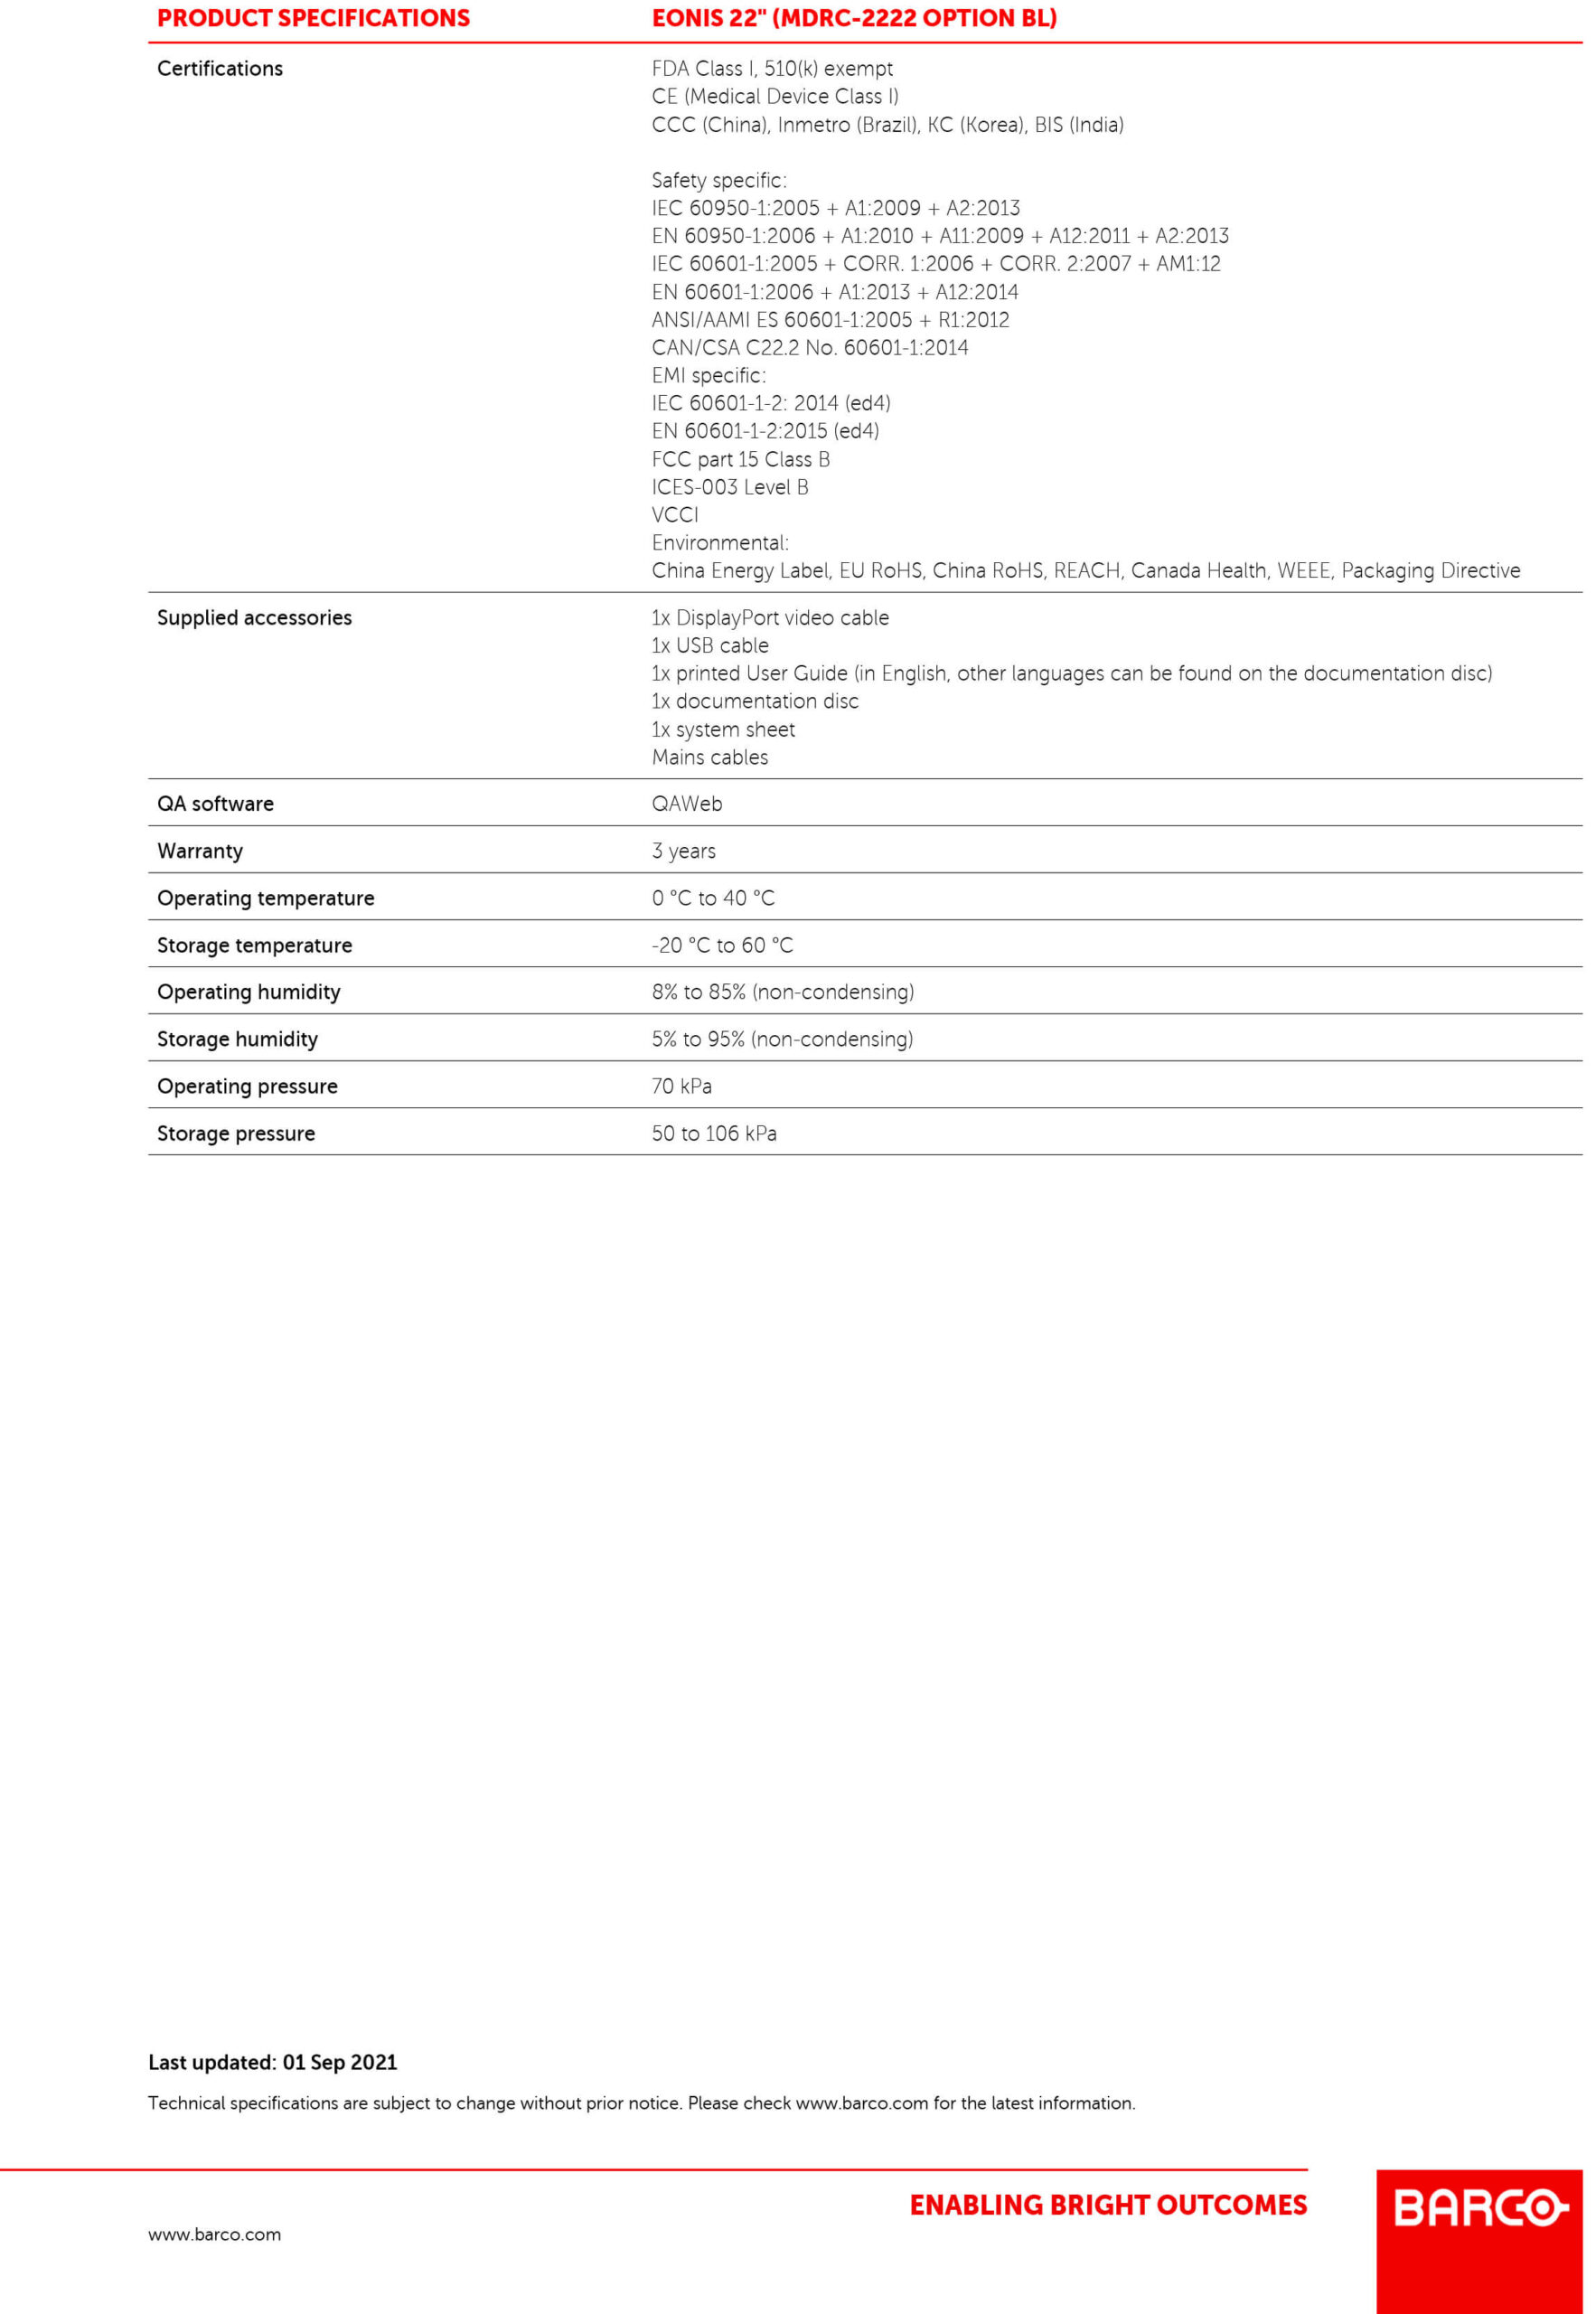

سیستم پزشکی QAWeb

سیستم پزشکی QAWeb یک سرویس آنلاین بوده که به کاربران کمک میکند تا از تضمین کیفیت با درجه بالا اطمینان حاصل کنند. این سیستم به عنوان یک ابزار مبتنی بر وب میتواند برای کالیبراسیون، تضمین کیفیت و مدیریت سرمایه، به آسانی استفاده شود.

مزایای سیستم پزشکی QAWeb عبارتند از:

– افزایش زمان فعالیت ایستگاههای کاری

– تضمین کیفیت و ثبات تصاویر در هر لحظه

– عدم وقفه در روند مشاهده تصاویر